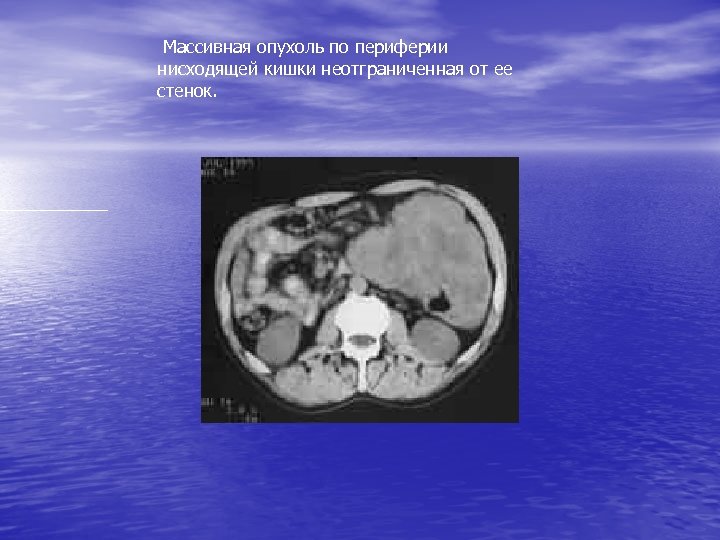

Массивная опухоль по периферии нисходящей кишки неотграниченная от ее стенок.